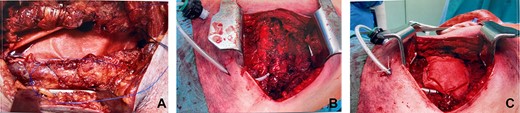

A small skin incision was made on the exact location of the lung hernia cutaneous, subcutaneous and muscles states preparation followed. Using a sandwich technique, we inserted a sublay bovine pericardium mesh reinforced with pericostal sutures, followed by onlay mesh placement. Redon 16 catheters were placed, and the incision was closed with continuous sutures (Fig. 3a–c).

(a) Insertion of the bovine pericardium mesh in sublay position and fixtation with continuous sutures, (b) the reinforced chest wall closure with pericostal sutures and (c) the onlay Insertion of the bovine pericardium mesh and the insertion of Redon catheters over the sublay inserted mesh and under the ICS.